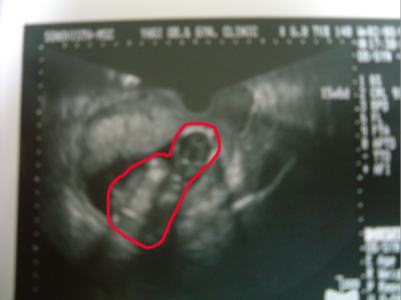

今日は産婦人科に行ってきました。

赤ちゃんは順調でスクスクと大きくなっているみたいで